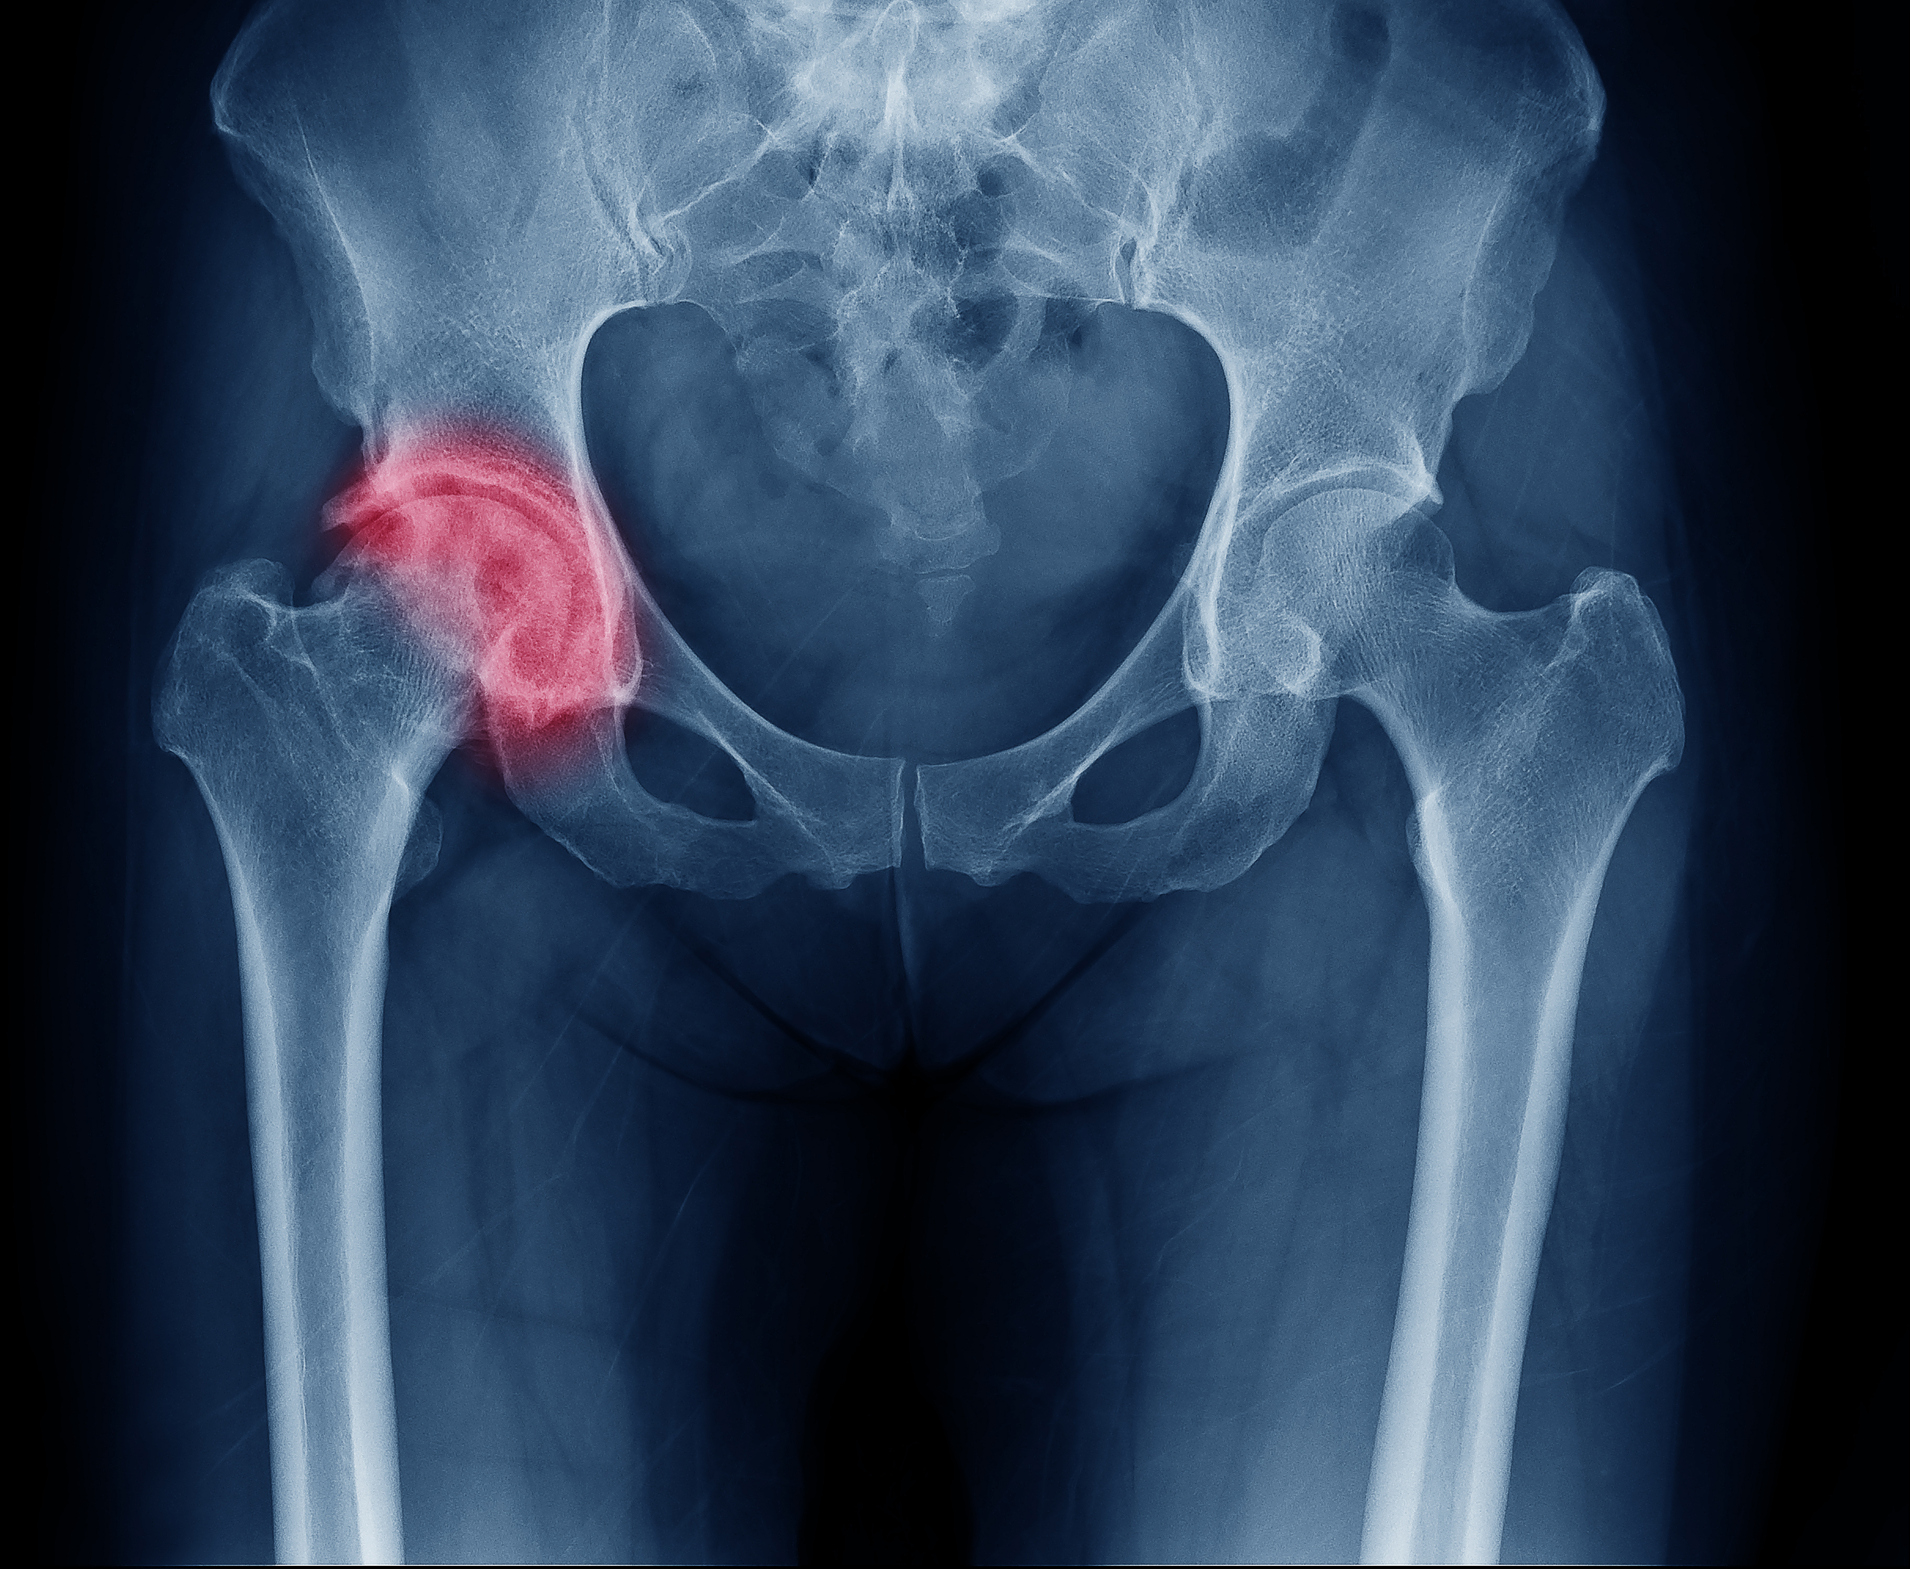

Рентгеновские снимки: Синовит тазобедренного сустава